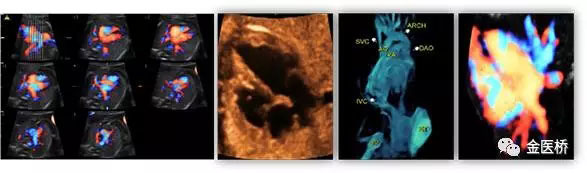

胎兒心臟超聲又名胎兒超聲心動圖,是一種無創(chuàng)、安全的影像學檢查,也是胎兒期唯一有效的能夠顯示胎兒心臟結構、血流及評估心臟功能的影像學手段,在產前及時診斷,隨診,預后判斷至關重要,不可替代。